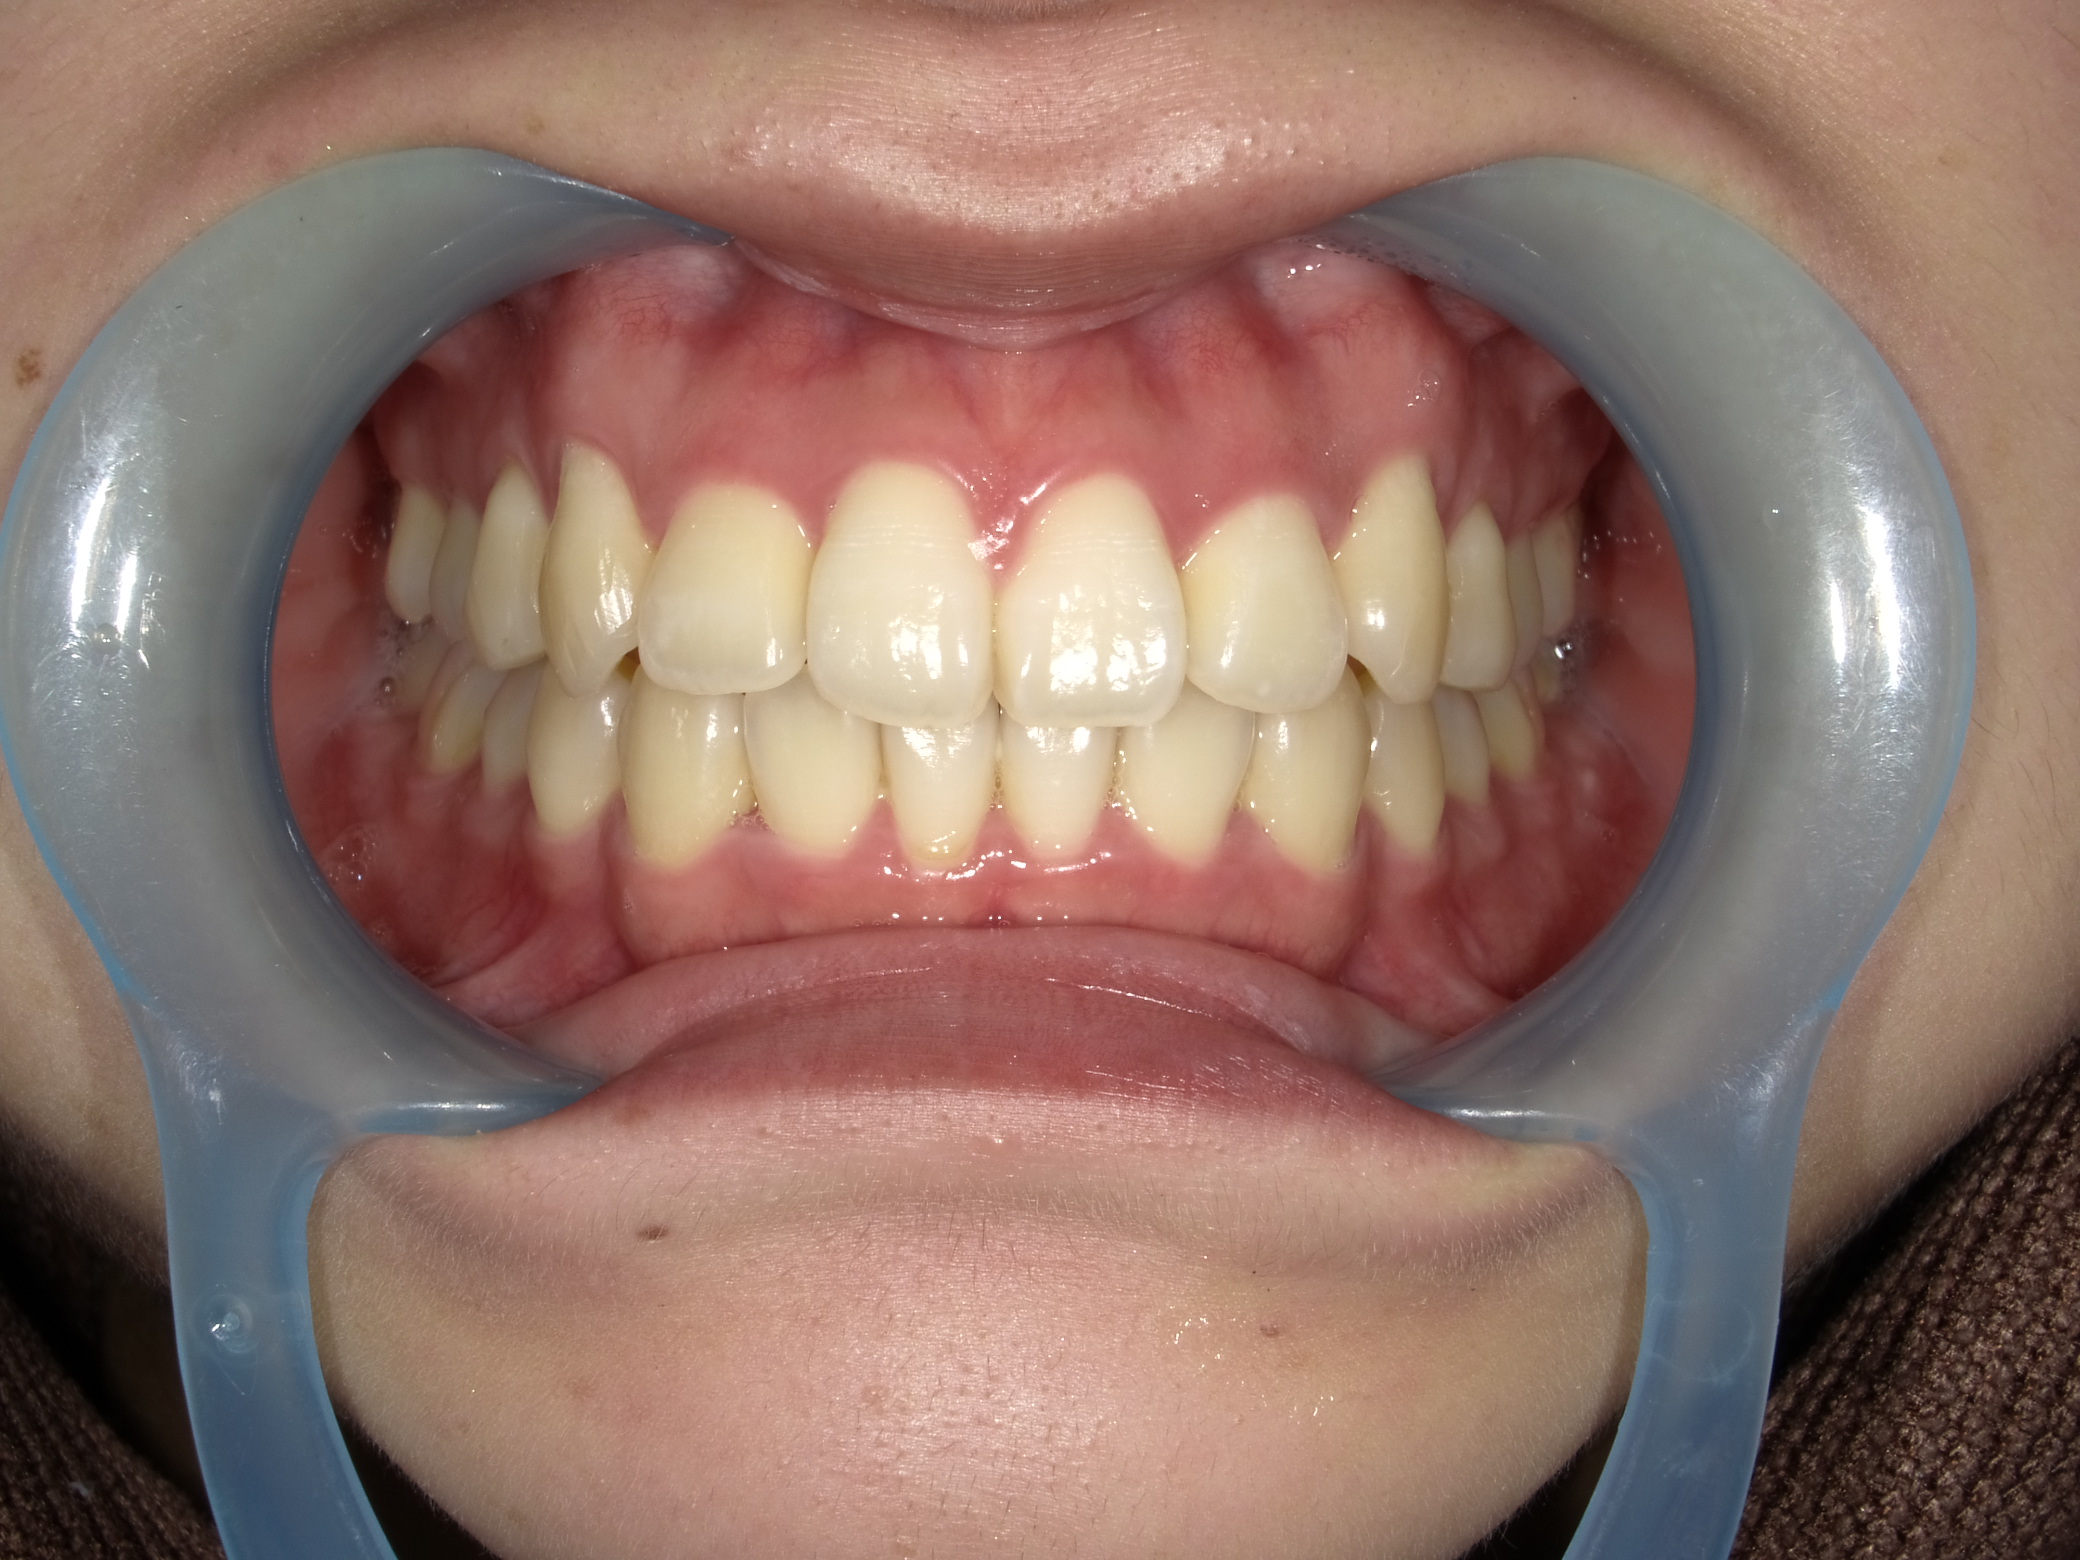

◾️治療後の状態(After)

インビザライン矯正により前歯部の歯の重なりが解消され、犬歯を含む前歯が歯列内に収まりました。

前歯の突出感(出っ歯の印象)も軽減され、全体として自然で違和感の少ない歯並びに仕上がった症例です。

◾️治療内容の概要

治療方法:マウスピース型矯正装置(インビザライン)

治療期間:6ヶ月

◾️矯正治療に伴うリスク・注意点

歯列矯正中に伴う疼痛・咬合痛・う蝕・歯肉退縮などのリスクがあります。治療期間や費用については個人差があります。